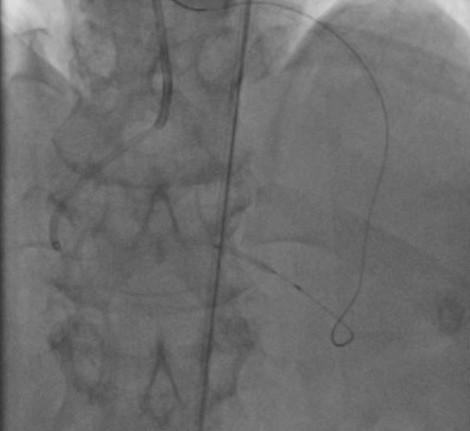

G.H.M.S.S., 46 anos, com hipertensão, diabetes, dislipidemia, história familiar de doença arterial coronariana (DAC) precoce e ex-tabagista. Foi internado em novembro de 2021 e diagnosticado com acidente vascular cerebral (AVC). Durante o internamento, realizou ecocardiograma para investigar possíveis causas do AVC, que evidenciou fração de ejeção de 46% com hipocontratilidade do ventrículo esquerdo mais acentuada em parede inferior. Na ocasião, tinha desconforto retroesternal em aperto e dispneia aos esforços. A angiotomografia demonstrou DAC multiarterial e ao realizar cateterismo foi visto: descendente anterior (DA) com lesão moderada no óstio e duas lesões graves (90%) no 1/3 proximal; circunflexa (Cx) com lesão grave no 1/3 proximal e no 1/3 médio; 1º marginal (Mg) com lesão grave no óstio; coronária direita (CD) dominante ocluída no 1/3 proximal; circulação colateral da coronária esquerda para a descendente posterior grau III. Foi indicado cirurgia de revascularização miocárdica, porém o paciente recusou e insistiu para realizar o procedimento via percutânea. Dessa forma, realizou angioplastia transluminal coronária em 02/22 que tratou as lesões em DA, Cx e 1º Mg e foi optado por tratar a oclusão crônica em CD posteriormente.Em julho, foi feito o procedimento com a tentativa de acessar retrogradamente o 1/3 distal da coronária direita com a corda guia Samurai e posteriormente com a corda guia 0,014 Pilot 150 com o suporte do microcateter Mamba sem sucesso, com dissecção da capa distal da oclusão. Então, houve tentativa de cruzar por via anterógrada com a guia Fighter, também sem sucesso. Terceira tentativa de puncionar a capa proximal da oclusão com a guia Hornet 10 também falhou, porque a guia não seguiu a curvatura da CD e pareceu seguir pela luz de um marginal direito. Por último, foi optado por utilizar um novo microcateter Mamba e realizar uma dissecção proximal da CD com um balão e seguir com a guia Pilot 150 e o microcateter através do espaço sub-intimal até o 1/3 distal da CD, realizando dilatação do espaço com balão. Guiado por ultrassom intra-coronário, foi feito o implante de stents em todo o segmento da CD no espaço sub-intimal e realizados, ainda, pós dilatação intra-stent. Ao final do procedimento, o ultrassom demonstrou boa expansão, porém com poucas áreas de má aposição, sendo optado por não realizar nova pós-dilatação, uma vez que havia ruptura do vaso com dilatação agressiva no espaço sub-intimal. Após o procedimento, o paciente evoluiu estável e assintomático, recebendo alta hospitalar depois de 3 dias com AAS e Ticagrelor.